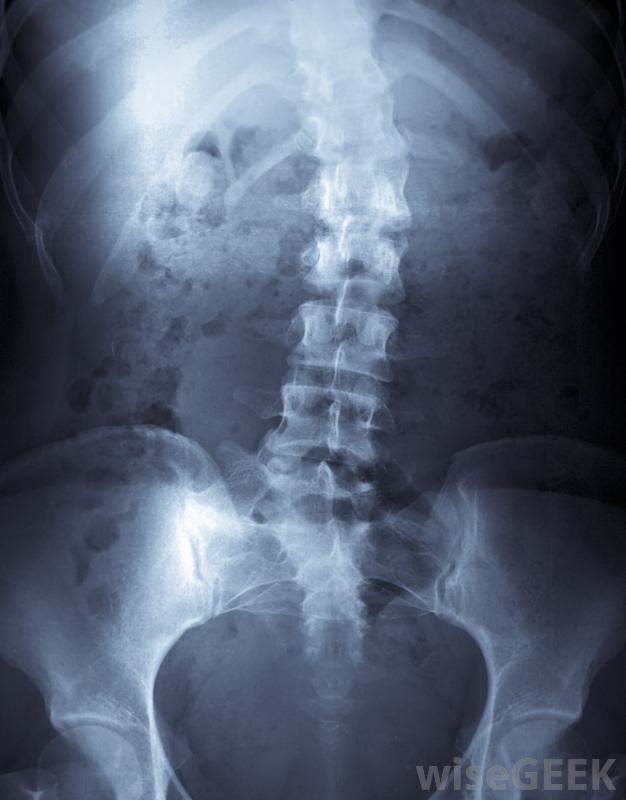

脊柱融合術可用于治療脊柱側凸,脊柱融合術是兩個或兩個以上的椎骨融合在一起的一種醫療程序。這可能有很多原因,但最常見的是脊柱側凸的矯正。外科醫生將脊柱伸直并在椎骨之間插入尸體骨尸體的骨頭就像一座橋梁,將脊椎骨連接在一起。一旦愈合,脊椎將保持筆直,融合骨阻止脊柱側凸的進一步發展。

脊柱融合是兩個或多個椎骨融合在一起的醫療過程。